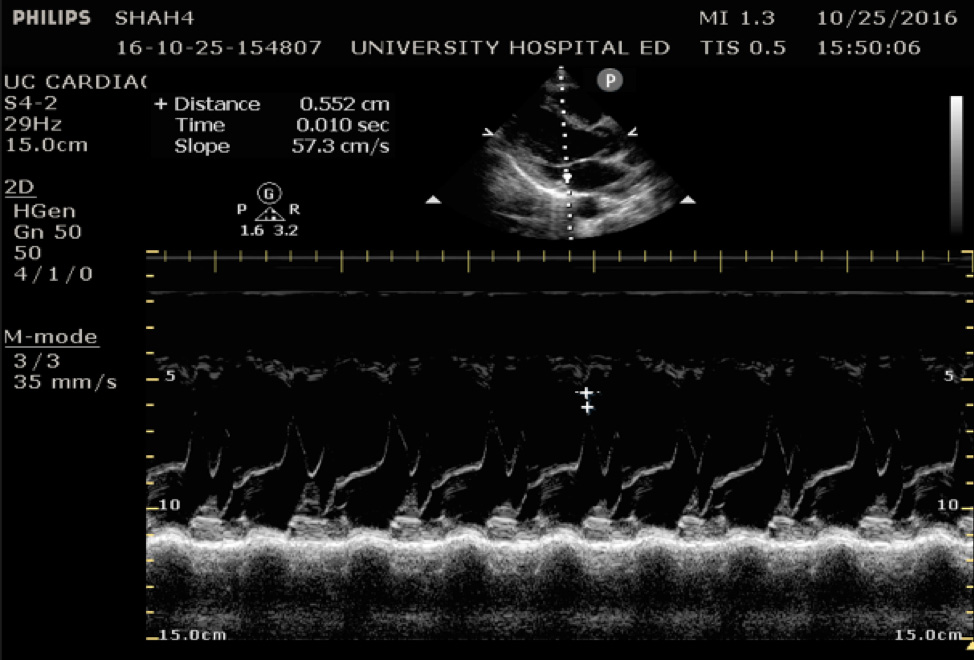

The cardiac component is essential to evaluation of a hypotensive patient as it can provide valuable information about cardiac physiology and etiology of shock. The goal of the cardiac portion of the examination is to classify presence or absence of pericardial effusion, pericardial tamponade, evaluate left and right ventricular contractility and chamber size and thus link these findings to the etiology of shock. Pericardial effusion with tamponade may be identified as a cause of obstructive shock. As fluid and pressure in the pericardial sac increases, early diastolic collapse of the right ventricular free wall is seen. (Video 1) This can be assessed visually in the parasternal long view by placing an M-mode line through the right ventricle (RV) and left ventricle (LV), including the interventricular septum and anterior leaflet of the mitral valve. (Figure 3) This allows for easy identification of right ventricular diastolic collapse, which is indicative of tamponade physiology.

Figure 3. Right ventricular diastolic collapse viewed in M-mode. Note motion of mitral valve leaflet, in the mid-field. Valve opening indicates diastole, which can then be compared to the collapse of the right ventricle in the near field.